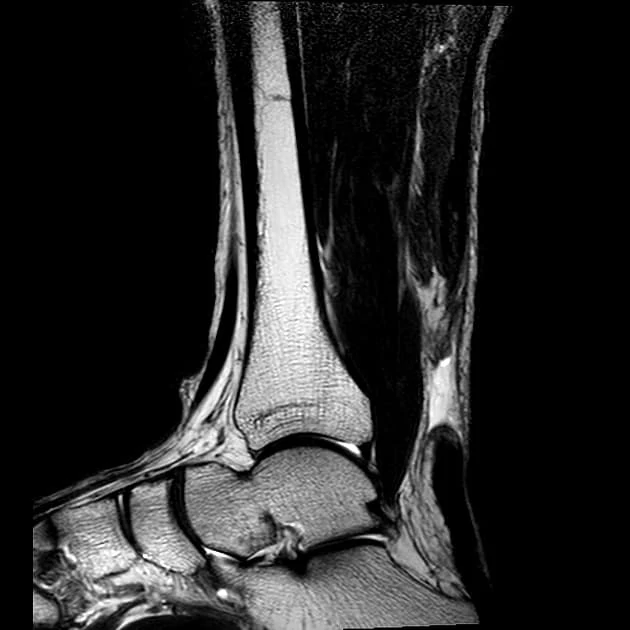

- U određenim slučajevima, za jasnu dijagnozu su nekad potrebni i dodatni pregledi kao što je MR – magnentna rezonanca. Ahilova tetiva se zapravo najbolje procenjuje MR i UZ pregledom.